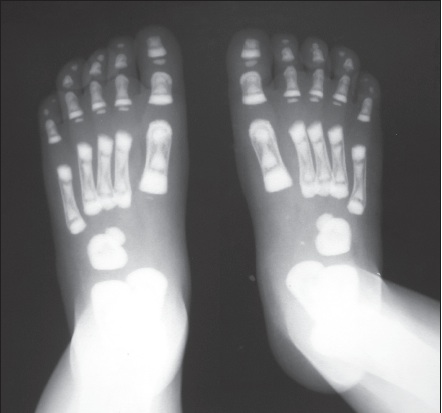

The child has osteopetrosis. The radiographs show diffuse osteosclerosis and dramatically increased bone density throughout the axial and appendicular skeleton. There is diffuse bone sclerosis in the hands with widening of the distal radial metaphyses (A, arrows) and a "bone-within-a-bone appearance"--typical of osteopetrosis--in virtually all the metacarpals and phalanges. Bone sclerosis is also apparent in the feet; the bone-within-a-bone appearance is most prominent in the metatarsals (B, arrows). A chest radiograph demonstrates diffuse bone sclerosis and numerous old fractures of the anterolateral ribs bilaterally (C, arrows).